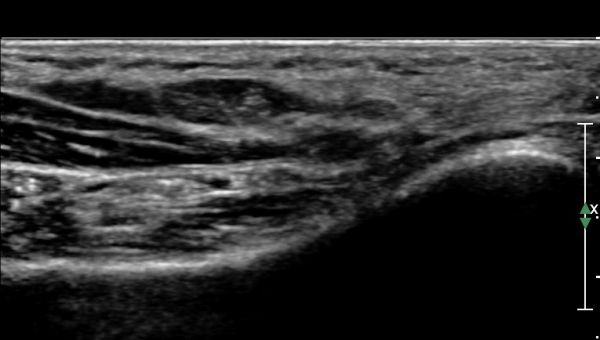

ÆÄ¿öµµÇ÷¯¸¦ Àû¿ëÇÏ´Ï ½Å°æ°ú Ç÷°üÀÇ ±¸ºÐÀÌ ¶Ñ·ÇÇÏ´Ù(»çÁø 5).